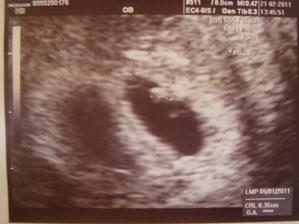

Pidižva č.2 a č.3... :o)